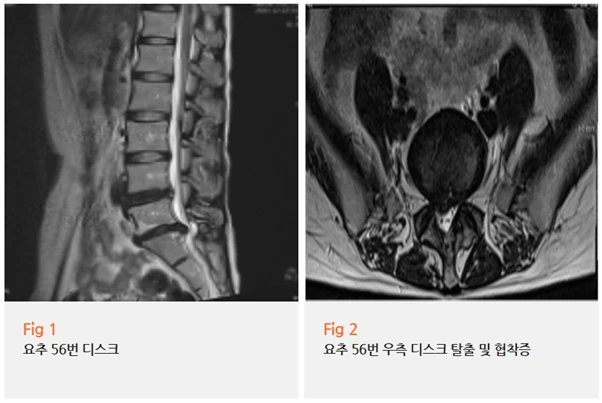

MRI 검사 결과,

1️⃣ 요추 4-5번, 5번-천추1번의 전방전위증으로 인한 심한 신경협착

2️⃣ 왼쪽 좌골낭염

이 두 가지가 동시에 발견됐어요.

전방전위증이란 위쪽 척추뼈가 아래쪽 척추뼈보다 앞으로 밀려나가는 상태를 말하는데요,

이렇게 되면 척추관이 좁아지면서 신경이 눌리게 됩니다.

누운 자세에서는 척추의 정렬이 바뀌면서

이 눌린 신경에 더 많은 압력이 가해질 수 있어요.

그래서 누웠을 때 오히려 통증이 심해지는 거죠.